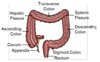

What lies within the upper right quadrant if we divide the abdomen into quatres from the umbilicus?

- right lobe of the liver

- gall bladder

- duodenum (first part of SI)

- head of Pancreas

- hepatic flexure of colon

- small part of ascending and transverse colon

What lies within the upper left quadrant if we divide the abdomen into quatres from the umbilicus?

- stomach

- spleen

- left lobe of liver

- body of pancreas

- splenic flexure of colon

- part of transverse and descending colon

What lies within the lower left quadrant if we divide the abdomen into quatres from the umbilicus?

- small intestine

- descending colon

- sigmoid Colon

What lies within the lower right quadrant if we divide the abdomen into quatres from the umbilicus?

- cecum

- appendix

- ascending colon

- small intestine